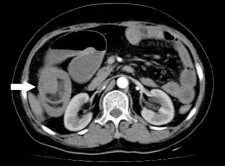

Hình 1.14. U mỡ ác tính tại dạ dày [86]

Ruột non: Tác giả Mohammad Amx (Mỹ) là người đầu tiên thông báo trường hợp u mỡ ác tính của ruột non (1957), khối u này gây tắc ruột do lồng ruột non trên một đoạn 15 cm [95], đây là một trong những biến chứng do u gây ra như tắc ruột, xoắn ruột, chảy máu [84, 96]. Một trong những biến chứng hiếm gặp khác mà tác giả Hasashi (Nhật Bản) và cộng sự đã mô tả là thủng ruột gây viêm phúc mạc do u mỡ ác tính gây ra, đây là một trong hai trường hợp trong y văn mà chúng tôi tìm thấy cùng với bài viết của tác giả người Ba Lan đăng năm 1984 [97]. Chẩn đoán trước mổ bằng lâm sàng thường khó khăn, nhờ có chụp cắt lớp hoặc viên camera nội soi mới cho gợi ý chẩn đoán [98].